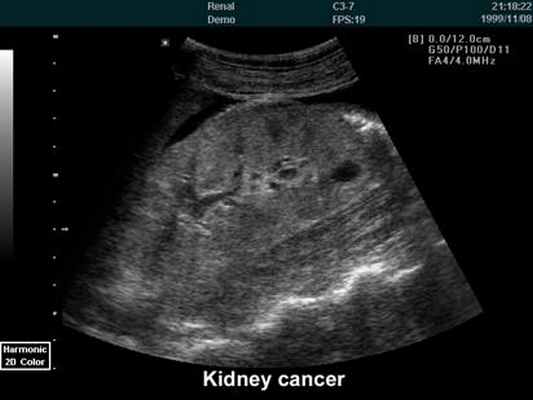

При проведении УЗИ врач оценивает выраженность диффузных изменений

почечной паренхимы, выявляет кисты, доброкачественные и злокачественные опухоли. УЗИ информативна

в выявлении патологических изменений надпочечников и предстательной железы –